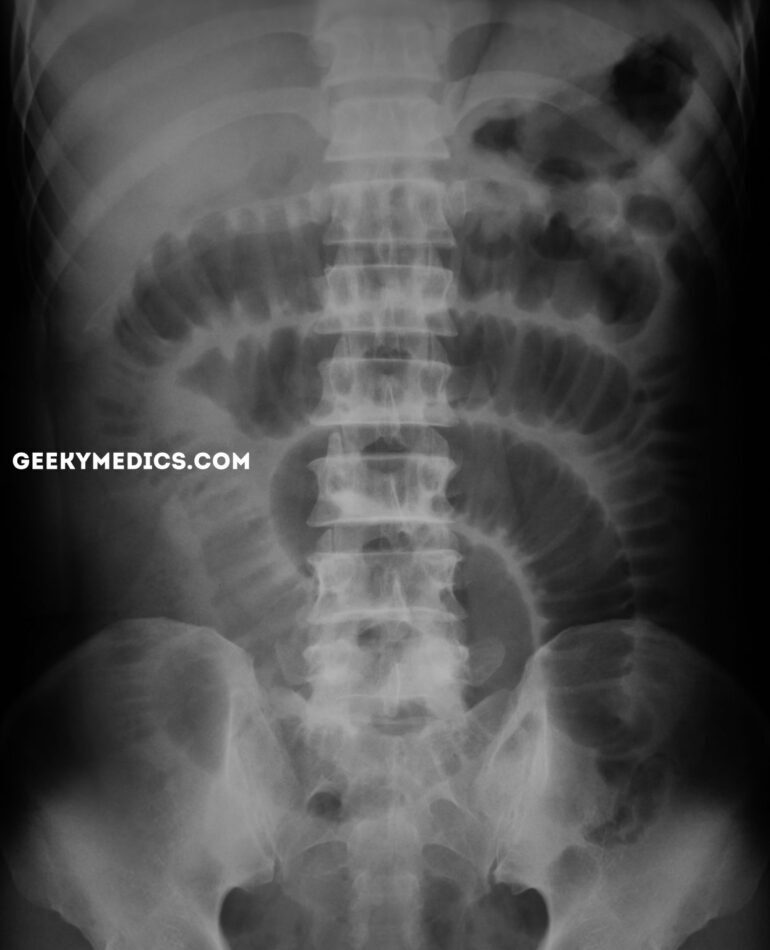

Q

what does this AXR show?

A

large bowel obstruction

- peripheral bowel loops

- large dilated bowel loops >6cm diameter

- haustra partially crosses diameter of bowel